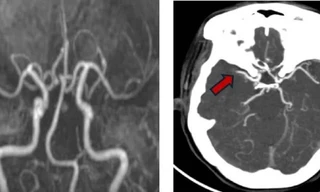

TPO - Tưởng như đã vượt qua cơn nguy hiểm sau lần đột quỵ đầu tiên, người phụ nữ 57 tuổi không ngờ lại đối mặt tiếp cơn đột quỵ thứ hai trong vòng chưa đầy 24 giờ.

TPO - Biến chứng rung nhĩ khiến nữ bệnh nhân rơi vào tình trạng đột quỵ liên tiếp 2 lần trong vòng 48 giờ. Người bệnh đã may mắn được các bác sĩ can thiệp kịp thời giúp qua cơn nguy kịch.